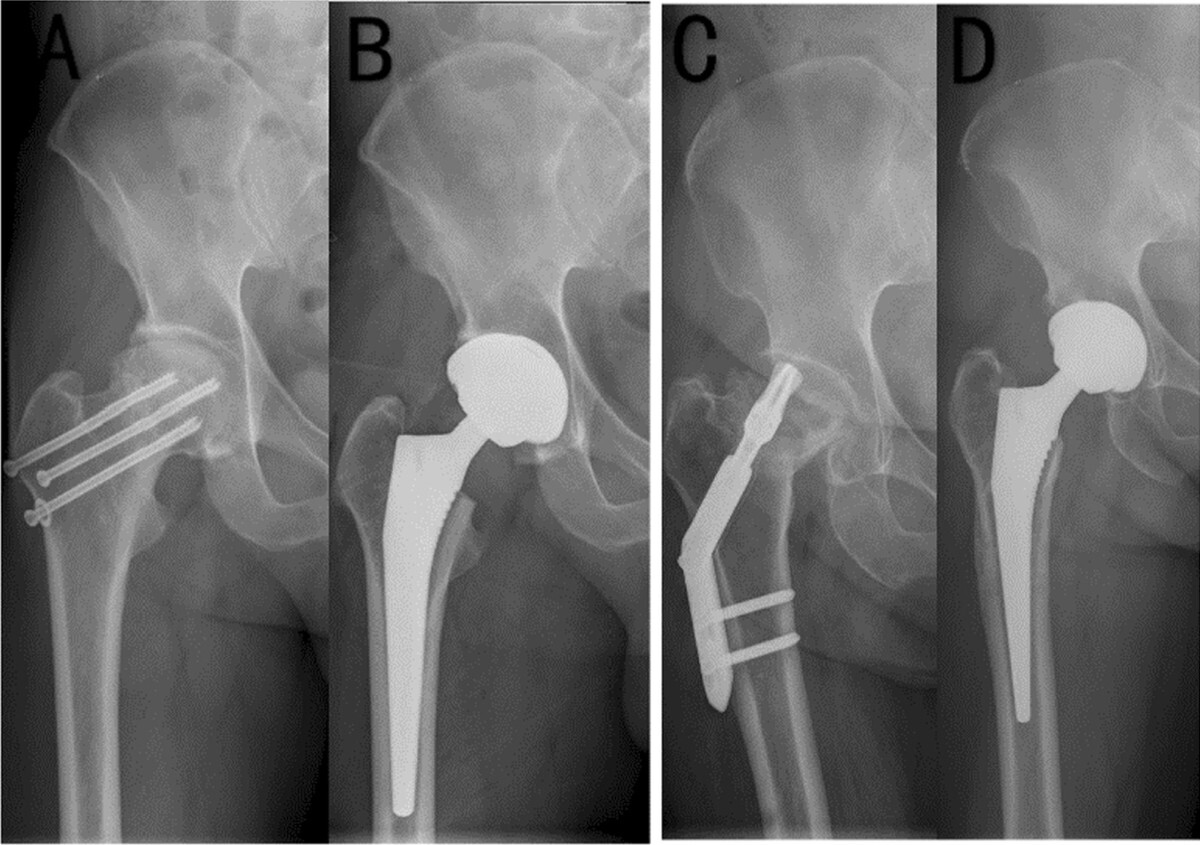

For minimally displaced FNFs, IF remains widely used, however failure rates are high. Dolatowski et al performed a randomised control trial demonstrating a reoperation rate of 43% after screw fixation compared with only 6% after HA.47 Posterior tilt ≥20° was the strongest predictor of fixation failure, leading many surgeons to treat these fractures as functionally displaced and recommend arthroplasty.29–31

For displaced FNFs, the choice between HA and THA is more nuanced. The HEALTH trial showed no difference in reoperation rates between THA and HA at 24 months, but small functional advantages for THA that did not exceed MCID.58 Mortality outcomes were equivalent, with 30-day rates of 7–10% in both groups.10,60 Registry data from Sweden and Norway confirm higher reoperation rates after HA due to acetabular erosion, but also higher early complication rates after THA, particularly dislocation and PPFF.20,46

Yu et al. in a meta-analysis reported that THA provides better hip function and quality of life compared with HA, albeit at the expense of longer operative times by approximately 20–30 minutes and greater intraoperative blood loss (p < 0.05) .71 Dislocation rates also remain higher following THA (2–5%) than HA (1–2%).61,71 Over the medium to long term, revision rates at 5–10 years tend to converge, as HA patients develop acetabular wear necessitating conversion to THA, while THA patients are predominantly revised for instability or PPFF.20,63